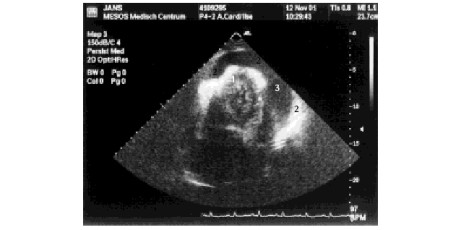

Van Gijn, Van den Berg en Van Lier beschreven een zeldzame hartchirurgische complicatie op een voor de huisarts lezenswaardige wijze (H&W 2003;46:624- 6). Ze vestigen de aandacht op de pulsus paradoxus, die gemakkelijk en snel te meten zou zijn en waarvan de aanwezigheid sterk wijst op een…